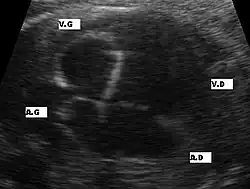

Aspects échographiques avant la naissance

Plusieurs aspects peuvent se rencontrer: une hypertrophie ou une hypoplasie du ventricule gauche ou un ventricule gauche quasiment sans aucune contraction sans aucun flux sanguin au doppler. La circulation du sang étant alors uniquement assuré par le ventricule droit. Le pronostic de cette maladie dépendra du ventricule droit. La visualisation directe d'une ouverture incomplète de la valve aortique et la présence de turbulence au niveau aortique par doppler couleur sont les deux signes directes de cette pathologie mais difficiles à visualiser lors de l'échographie obstétricale. Une brillance anormale du ventricule gauche est un signe de souffrance myocardique par diminution du flux sanguin des coronaires.